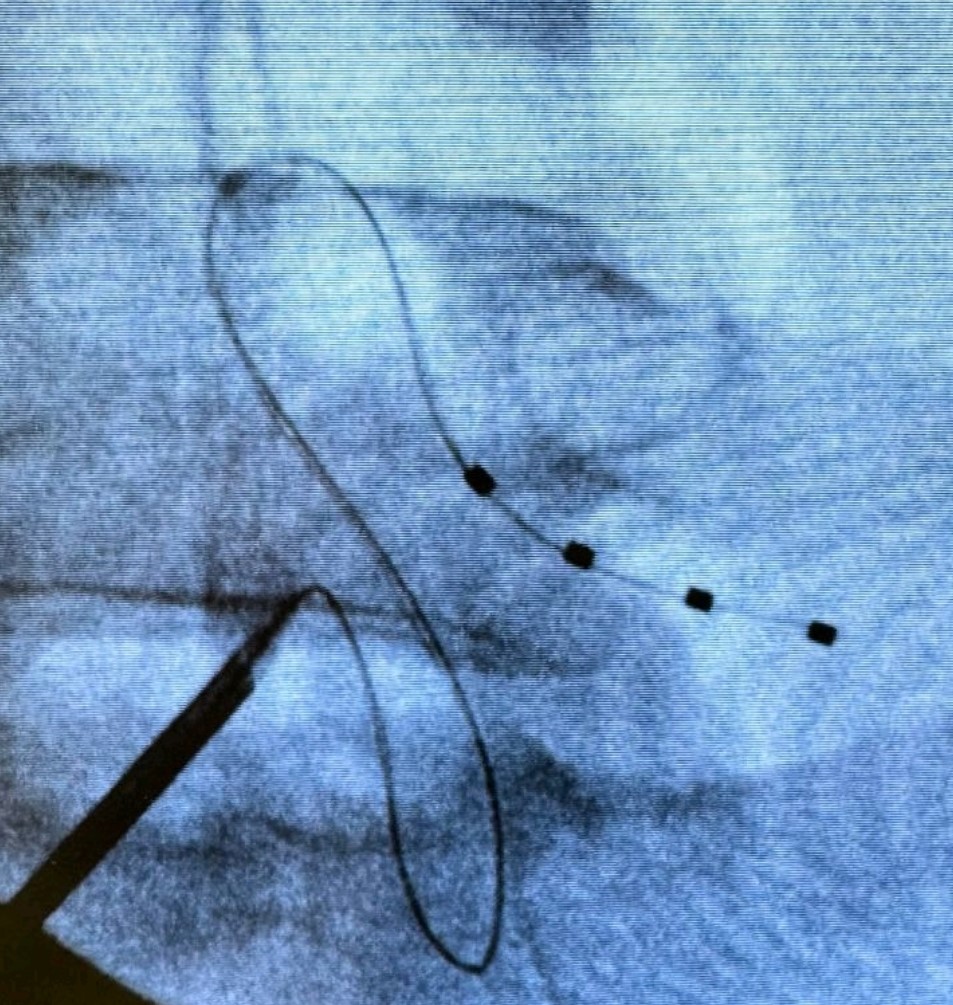

Η τεχνική της διέγερσης του DRG είναι σχεδόν πανομοιότυπη με τη τεχνική διέγερσης του νωτιαίου μυελού. Ωστόσο, στόχο της νευροδιέγερσης εδώ αποτελεί το συγκεκριμένο γάγγλιο και όχι ο νωτιαίος μυελός. Τα γάγγλια της ραχιαίας ρίζας βρίσκονται στα μεσοσπονδύλια τρήματα.

Η διέγερση του DRG αφορά στην εμφύτευση ηλεκτροδίου που στέλνει ηλεκτρικά ερεθίσματα στη συγκεκριμένη περιοχή. Οι ώσεις αυτές διακόπτουν τη μετάδοση των σημάτων πόνου από το περιφερικό προς το κεντρικό νευρικό νευρικό σύστημα. Με απλά λόγια, η διέγερση του γαγγλίου τροποποιεί την αντίληψη του πόνου. Πριν την τελική εμφύτευση του ή των ηλεκτροδίων και τη σύνδεση αυτών με τη γεννήτρια, προηγείται διάστημα δοκιμαστικής διέγερσης με φορητή, εξωτερική γεννήτρια.